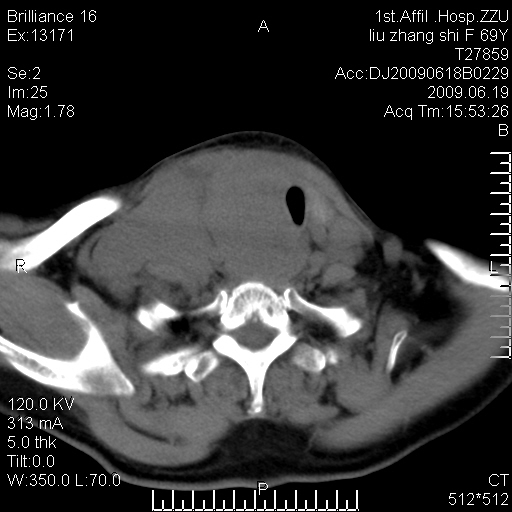

标题: CT26782:女,69岁,颈部占位,3天后公布病理结果。

【病理证实系列】女,69岁,颈部占位,有病理结果,3天后公布。(由于病例时间较久,临床资料不全,请网友见谅)本系列将有几百种常见、少见及罕见病例,均经病理证实。病例资料来自郑州大学第一附属医院。与网友共享,本人有空就发。

甲状腺癌并颈部淋巴结转移。感谢楼主的良苦用心,谢谢。

甲状腺癌并颈部淋巴结转移。

需与鼻咽癌鉴别!

支持甲状腺癌广泛侵及周围结构并颈部淋巴结转移。

鉴别:淋巴瘤、恶性神经源性病变、恶性纤维组织细胞瘤。

病理结果:颈部非霍奇金淋巴瘤。